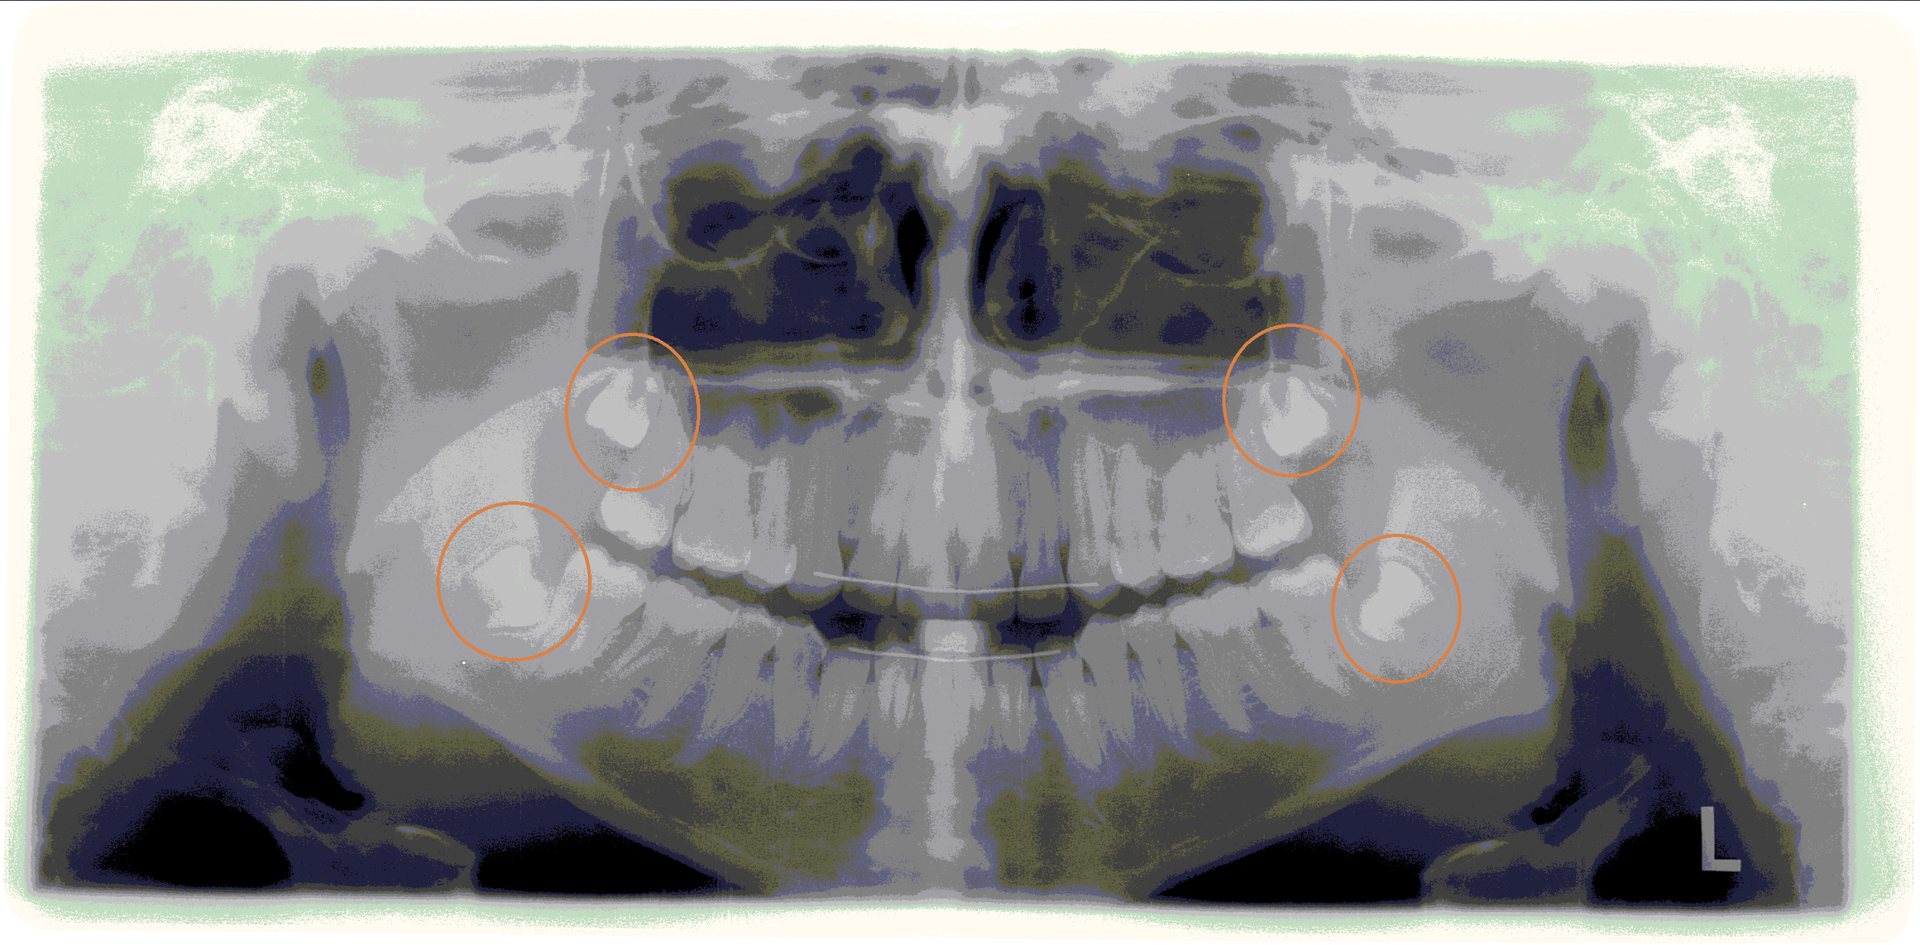

Unsere erfahrenen Zahnärztinnen setzen moderne digitale Röntgengeräte ein. So können aussagekräftige Röntgenbilder erstellt werden. Zudem profitieren Sie von einer deutlich geringeren Strahlenbelastung.